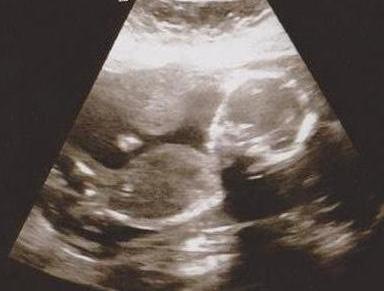

I don't really like the person that did my ultrasound. I only got 4 pics and 2 were profiles. Can anyone tell the gender from these?Attachment 4853Attachment 4854

Girl!

Girl

Girl~

Girl :babyf:

Girl congrats

Thanks! everyone. She said girl but it was so quick and she did not print many pics. I am looking into a 4d place so maybe we can get better pictures and so we can enjoy getting to see our baby. It just seemed rushed and uninterested. Maybe I am just spoiled by my old ob and he did ultrasounds in office.

That's a girl! Congrats :)